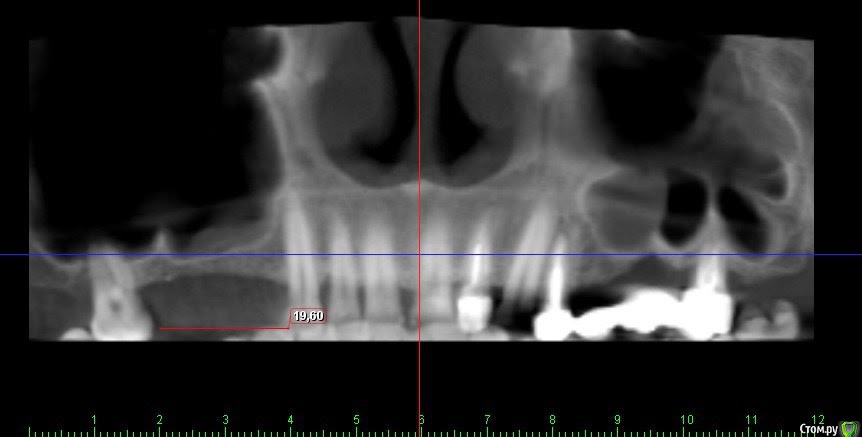

Kovalov Igor Опубликовано 19 мая, 2016 Поделиться Опубликовано 19 мая, 2016 (изменено) Здравствуйте уважаемые форумчане! Нужен совет по повторному синуслифтингу....3 месяца назад проводилась попытка синуслифтинга в 1 сегменте, отсутствие 14,15,16 зубов ... Разрез, формирование окна, в этом случае выбрал вход в синус с двух окон в проекции 14 и 16, получить перфу возле септы в области 16 когда отслаивал ... 14 отслойка без проблем... закрыл окна мембраной и ушил отправил погулять на 2,5-3 месяца.Вопрос как поступить ? Сделать одно большое окно? Как быть со спайками и как сложно их отделять ? Мембрану под перфу не подложил так как не делал ниразу этого... Кт после 3х месяцев ... Изменено 19 мая, 2016 пользователем Kovalov Igor Ссылка на комментарий

kriokov Опубликовано 19 мая, 2016 Поделиться Опубликовано 19 мая, 2016 пошел бы стандартно одним окном, да и первый раз думаю надо было одним окном идти, там не полная септа.Иногда приходиться остро работать на спайках как при расщеплении. Не знаю, но мне здесь одно здоровое окно видиться. И наверное зря Вы септу не спилили или не выкусили при первом заходе, если решили через три мес на повторный идти. Синус не плохо выглядит, думаю нормально все будет. 6 Ссылка на комментарий

red_butler Опубликовано 21 мая, 2016 Поделиться Опубликовано 21 мая, 2016 Куда вы 2гр L сыпите та? Тромбуете штоль?Даже еще раз пересмотрел срезы, Вы считаете что на такой операционной площади и при таком строении синуса расход будет меньше? 3 Ссылка на комментарий

Kovalov Igor Опубликовано 21 мая, 2016 Автор Поделиться Опубликовано 21 мая, 2016 Даже еще раз пересмотрел срезы, Вы считаете что на такой операционной площади и при таком строении синуса расход будет меньше?Ушло 2 грамма вы правы! ))) Спасибо всем за советы , ошибки были в первом случае малое и высоко расположенное окно, сделал в этот раз одно большое окно, спайки были только по периметру окна , было ощущение что окно начало заростать костью через три месяца, будто пластинка была поверх мембраны , может показалось ...Отслаивал до септы, графт 1,5 гр. в синус и 0,5 латерально от винтов и укрыл мембраной 25*25 владмива, мембрана не понравилась если честно ) Ссылка на комментарий